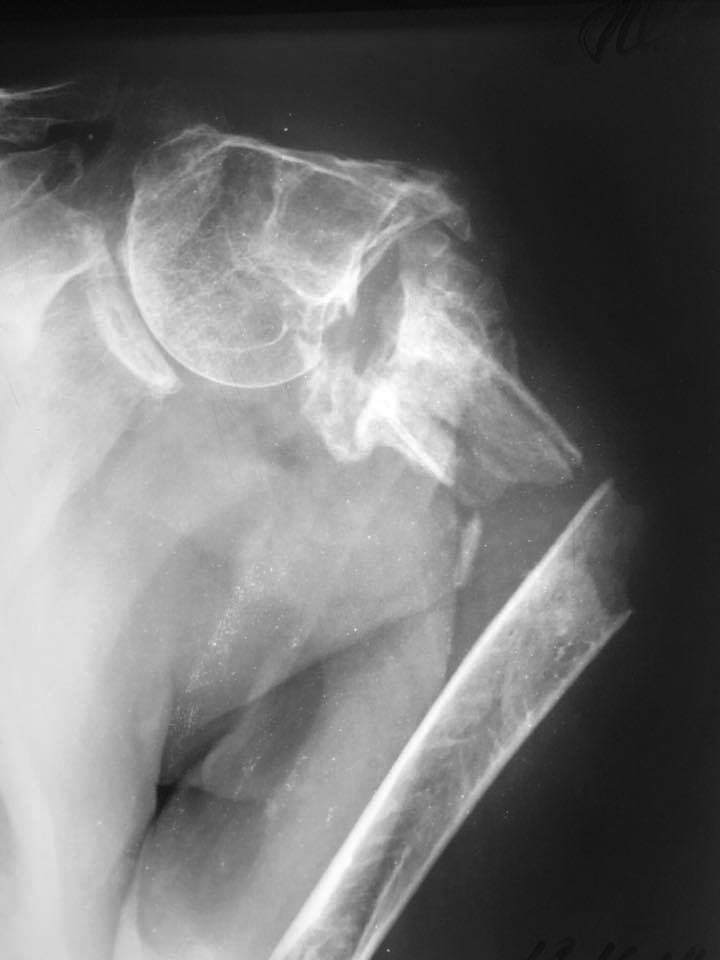

Новый перелом на фоне несращения плеча

Уважаемые коллеги, подскажите ...... в принятии решения? Первая травма 2 года назад. Вторая 2 недели.

Растянуть в дистракторе, вывести из головку варуса, лучше даже в вальгус, а потом гвоздь. Мультилок было бы идеально, другими гвоздями вряд ли будет стабильно

Уверен, что качество собственной жизни, этого пациента не особо волнует. Задача - не дать дистальному отломку перфорировать кожу. Все зависит от того, какие фиксаторы в вашем распоряжении имеются.... все? тогда любой наименее инвазивный